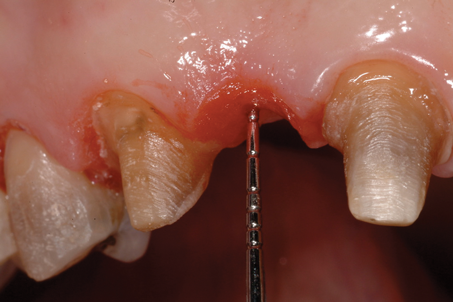

The distance between the bottom of the ovate pontic site and the alveolar bone is determined using a periodontal probe to sound for the bone. If the measured distance is 2 mm or greater (Figure 4), then there is adequate tissue thickness to meet the prosthetic biologic width requirements, and the provisional restoration can be cemented with provisional cement. However, if the tissue thickness is less than 2 mm, then there is not adequate tissue present to meet the prosthetic biologic width requirements (Figure 5), and the pontic site must be deepened using a teardrop-shaped diamond bur (Figure 6). The remaining soft tissue and enough alveolar bone are removed to result in the required 2-mm distance from the most subgingival aspect of the pontic to the alveolar bone. It is essential that the intaglio surface of the pontic be correctly contoured before the reshaping of the pontic site. The provisional bridge can then be cemented with a provisional cement and the provisional pontic will direct the regrowth of the soft tissue.

(12.) Bone sounding was performed to confirm that there was at least 2 mm from the base of the pontic sites to the alveolar bone.

Figure 12